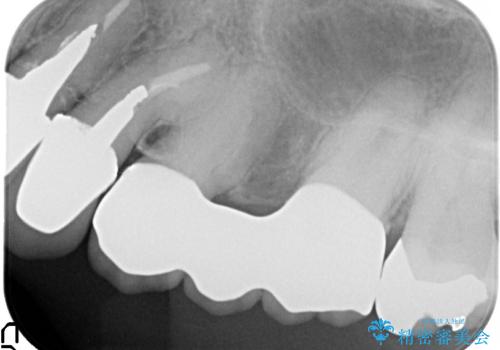

- 昔治療した左上56の延長ブリッジをきちんと治療しなおしたいといらっしゃった方の症例です。

古いブリッジを除去後、オールセラミッククラウンによる補綴を行いました。

今回用いたオールセラミッククラウンは、ジルコニアフレームという白い素材の上にセラミックを盛っているため審美性が非常に高いのが特徴です。

またジルコニアは人工ダイヤモンドの材料にも使われているほど高い強度を持っており、そのためオールセラミッククラウンは審美性だけでなく、奥歯やブリッジの補綴も可能とするクラウンです。